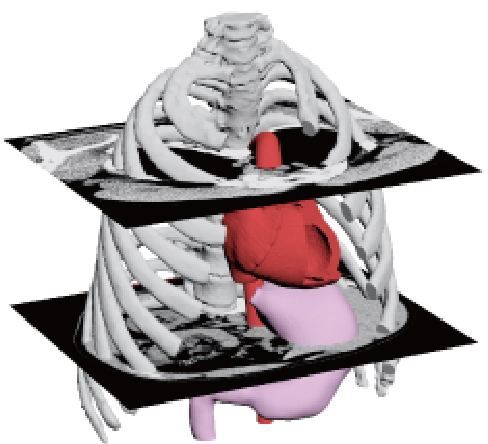

3D data extraction from medical CT and MRI data

3D data is essential for the production of models using 3D printers, but it is not always possible to

prepare 3D data in the medical field. In such a case, if you can provide us with DICOM data obtained from

CT or MRI, we can create precise 3D data.

JMC uses a software called "mimics" to construct precise skeletal and organ shapes from DICOM data. JMC

uses mimics software to construct precise shapes of skeletons and organs from DICOM data. By having

specialized engineers perform image processing using mimics, it is possible to extract only the areas of

interest and output higher quality 3D data with less distortion caused by metal products such as gold

teeth and pacemakers.